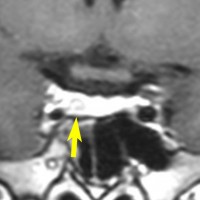

左は下垂体腺腫(緑の腫瘍)が内頚動脈に挟まれていることを示しています。

中央は手術前の下垂体腺腫で,視神経も正常下垂体も位置はわかりません。

右は手術翌日の画像です。黄色の矢印の先が残した正常下垂体組織です。桃色の矢印の先に視神経(視交叉)がはっきり見えています。術後の一時的な尿崩症がありました。クモ膜が残っているので髄液漏は生じませんでした。でも正常下垂体組織(黄色矢印)も視交叉も腫瘍に圧迫されてペラペラになっていますから,いつもうまく行くとは限りません。